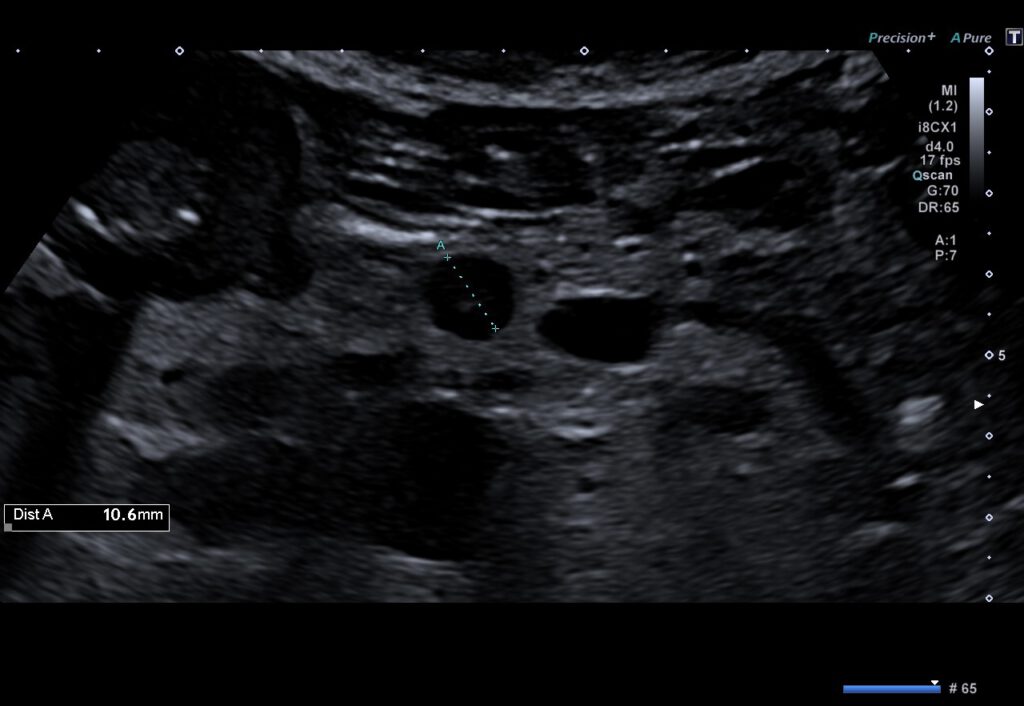

92-jährige Patientin mit Insulinom des Pankreas.

Wegen rezidivierender Hypoglykämien erfolgte die stationäre Behandlung. In der Abdomensonographie wurde ein kleiner echoarmer Tumor im Bereich des Pankreaskopfes auffällig, weswegen anschließend eine Endosonographie durchgeführt wurde. Hierbei bestätigte sich das Vorliegen eines hypervaskularisierten Tumors am Übergang zwischen Pankreaskopf und -korpus. Bei Multimorbidität und hohem Patientenalter wurde sich gemeinsam für die minimalinvasive Therapie der endosonographisch-geführten Ethanolinjektion entschieden. Nach Applikation von 1,5 ml 96% Ethanol stellte sich die Raumforderung in der kontrastmittelgestützten Sonographie-Kontrolle avital dar. Der Blutzuckerspiegel normalisierte sich rasch, die Patienten wurde ohne Notwendigkeit einer medikamentösen Therapie entlassen.